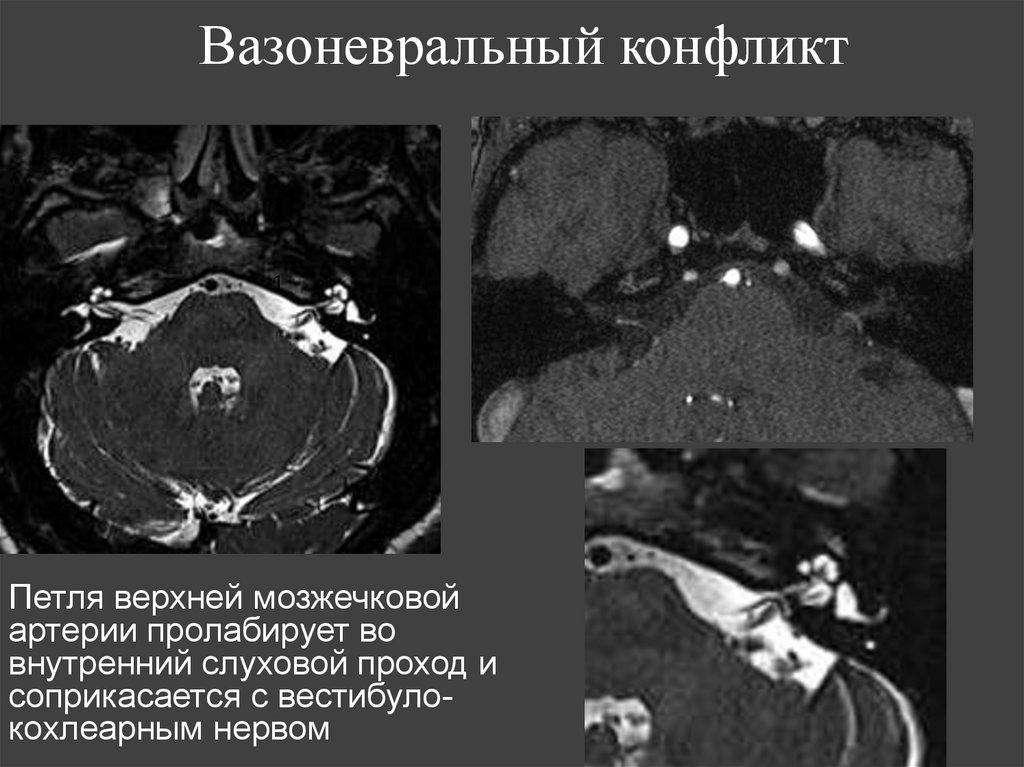

Вертикально идущие переломы чешуи

137. Вазоневральный конфликт

1

Петля верхней мозжечковой

артерии пролабирует во

внутренний слуховой проход и

соприкасается с вестибулокохлеарным нервом